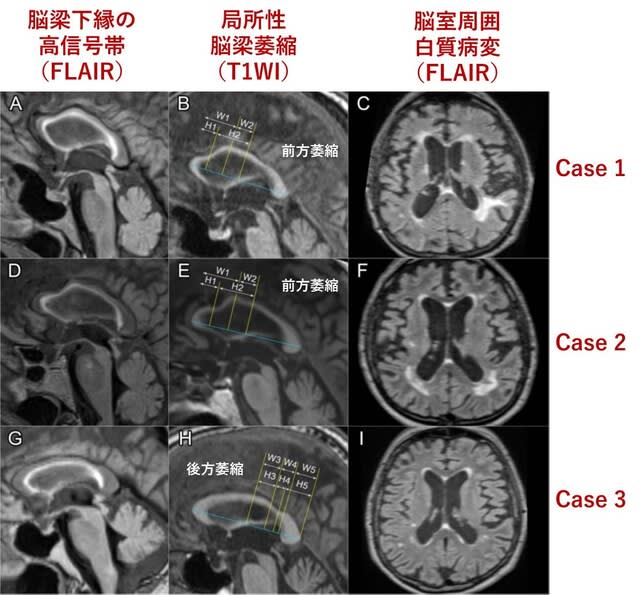

初学者のためのMRIの読み方 | 高橋睦正 |本 | 通販 | Amazon